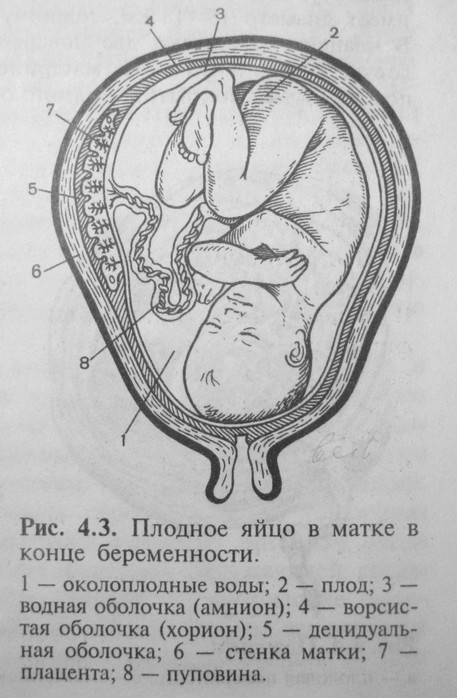

Околоплодный пузырь и плацента: структура и функции